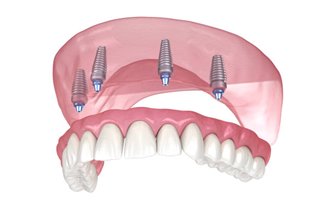

All-on-4 Dental Implants

A modern solution for full arch restoration using only four implants. All-on-4 implants are strategically angled to maximize bone support, making them ideal for patients with reduced bone volume — often eliminating the need for bone grafts.